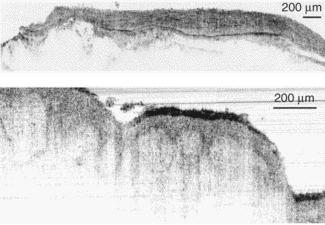

Recently, Wolfgang Drexler and his colleagues at the University of Vienna (Vienna, Austria), along with researchers from MenloSystems (Martinsried, Germany), have tested a broad-spectrum fiber laser emitting at 1375 nm to achieve sub-2-µm-axial-resolution OCT in nontransparent biological tissues.1 This resolution represents a 25% increase in axial OCT resolution. The tissues were ex vivo samples from a human artery and skin, which were imaged through thin layers of water to prevent dehydration and to optimize the index matching (see Fig. 1).

Individual layers and membranes are clearly visible in the artery and skin samples. The researchers believe this shows that an OCT system based on such a stable, low-cost, compact fiber laser has great potential for in vivo OCT clinical studies. To reach this point, laser performance must be improved by smoothing the emission spectrum and increasing the system output power two- to fivefold. A fiber-based OCT system capable of supporting the broad spectral output of the fiber laser will also have to be developed.